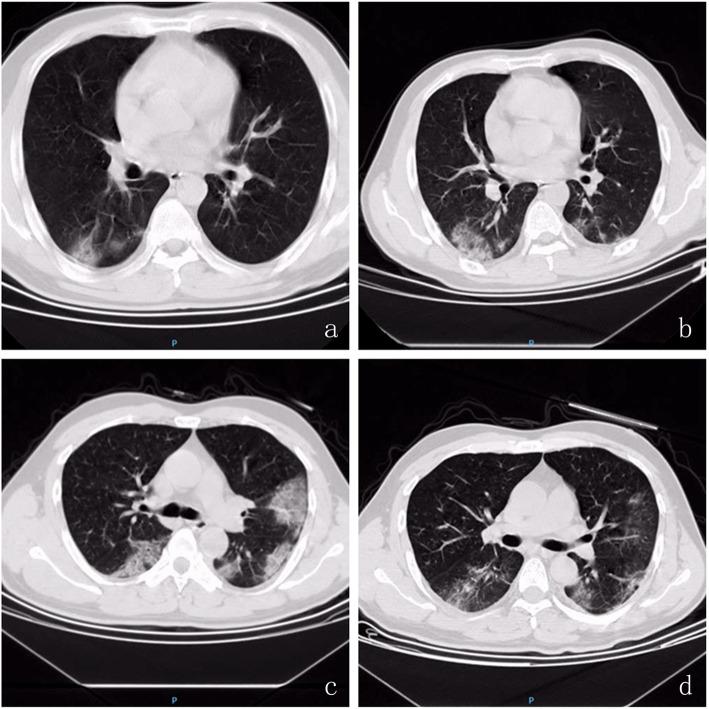

Nine (9/13) COVID-19 patients exhibited mild disease severity, and defined as second-generation human-to-human transmission cases. Most patients (11/13) had a history of travel to or from Wuhan. There were no differences in sex and age between the mild and severe cases (all P > 0.05). A moderate degree of fever (11/13), cough (13/13), and fatigue (8/13) were common symptoms; however, there was no statistical difference between mild and severe cases in this regard (all P > 0.05). Oxyhemoglobin saturation and oxygenation index decreased, and C-reactive protein (CRP) and serum amyloid A (SAA) levels were elevated in all patients with COVID-19 infection, with statistically significant differences between those with severe disease and mild infection (all P < 0.05). Twelve of 13 COVID-19 patients exhibited changes in chest CT imaging features, and time course changes were different between mild and severe cases (all P < 0.05).

Most cases of COVID-19 infection were second-generation human-to-human transmissions from Wuhan and were mild in severity. The clinical characteristics of COVID-19 varied. Oxyhemoglobin saturation, oxygenation index, CRP and SAA levels, and CT features were reliable parameters to evaluate the severity of COVID-19 infection. However, a few patients with mild COVID-19 disease lacked typical characteristics such as fever and changes in CT imaging features.

9 例(9/13)COVID-19 患者表现为轻症,定义为第二代人传人传播病例。大多数患者(11/13)有武汉旅行史或居住史。轻症和重症患者在性别和年龄上无差异(均 P>0.05)。中等程度发热(11/13)、咳嗽(13/13)和乏力(8/13)是常见症状;但轻症和重症患者在这方面无统计学差异(均 P>0.05)。所有 COVID-19 感染患者的血氧饱和度和氧合指数下降,C 反应蛋白(CRP)和血清淀粉样蛋白 A(SAA)水平升高,重症患者与轻症患者相比差异有统计学意义(均 P<0.05)。13 例 COVID-19 患者中有 12 例胸部 CT 影像学特征发生变化,轻症和重症患者的病程变化不同(均 P<0.05)。

大多数 COVID-19 感染病例为武汉二代人传人传播,且病情较轻。COVID-19 的临床特征各不相同。血氧饱和度、氧合指数、CRP 和 SAA 水平及 CT 特征是评估 COVID-19 感染严重程度的可靠参数。但少数轻症 COVID-19 患者缺乏发热等典型特征和 CT 影像学特征变化。